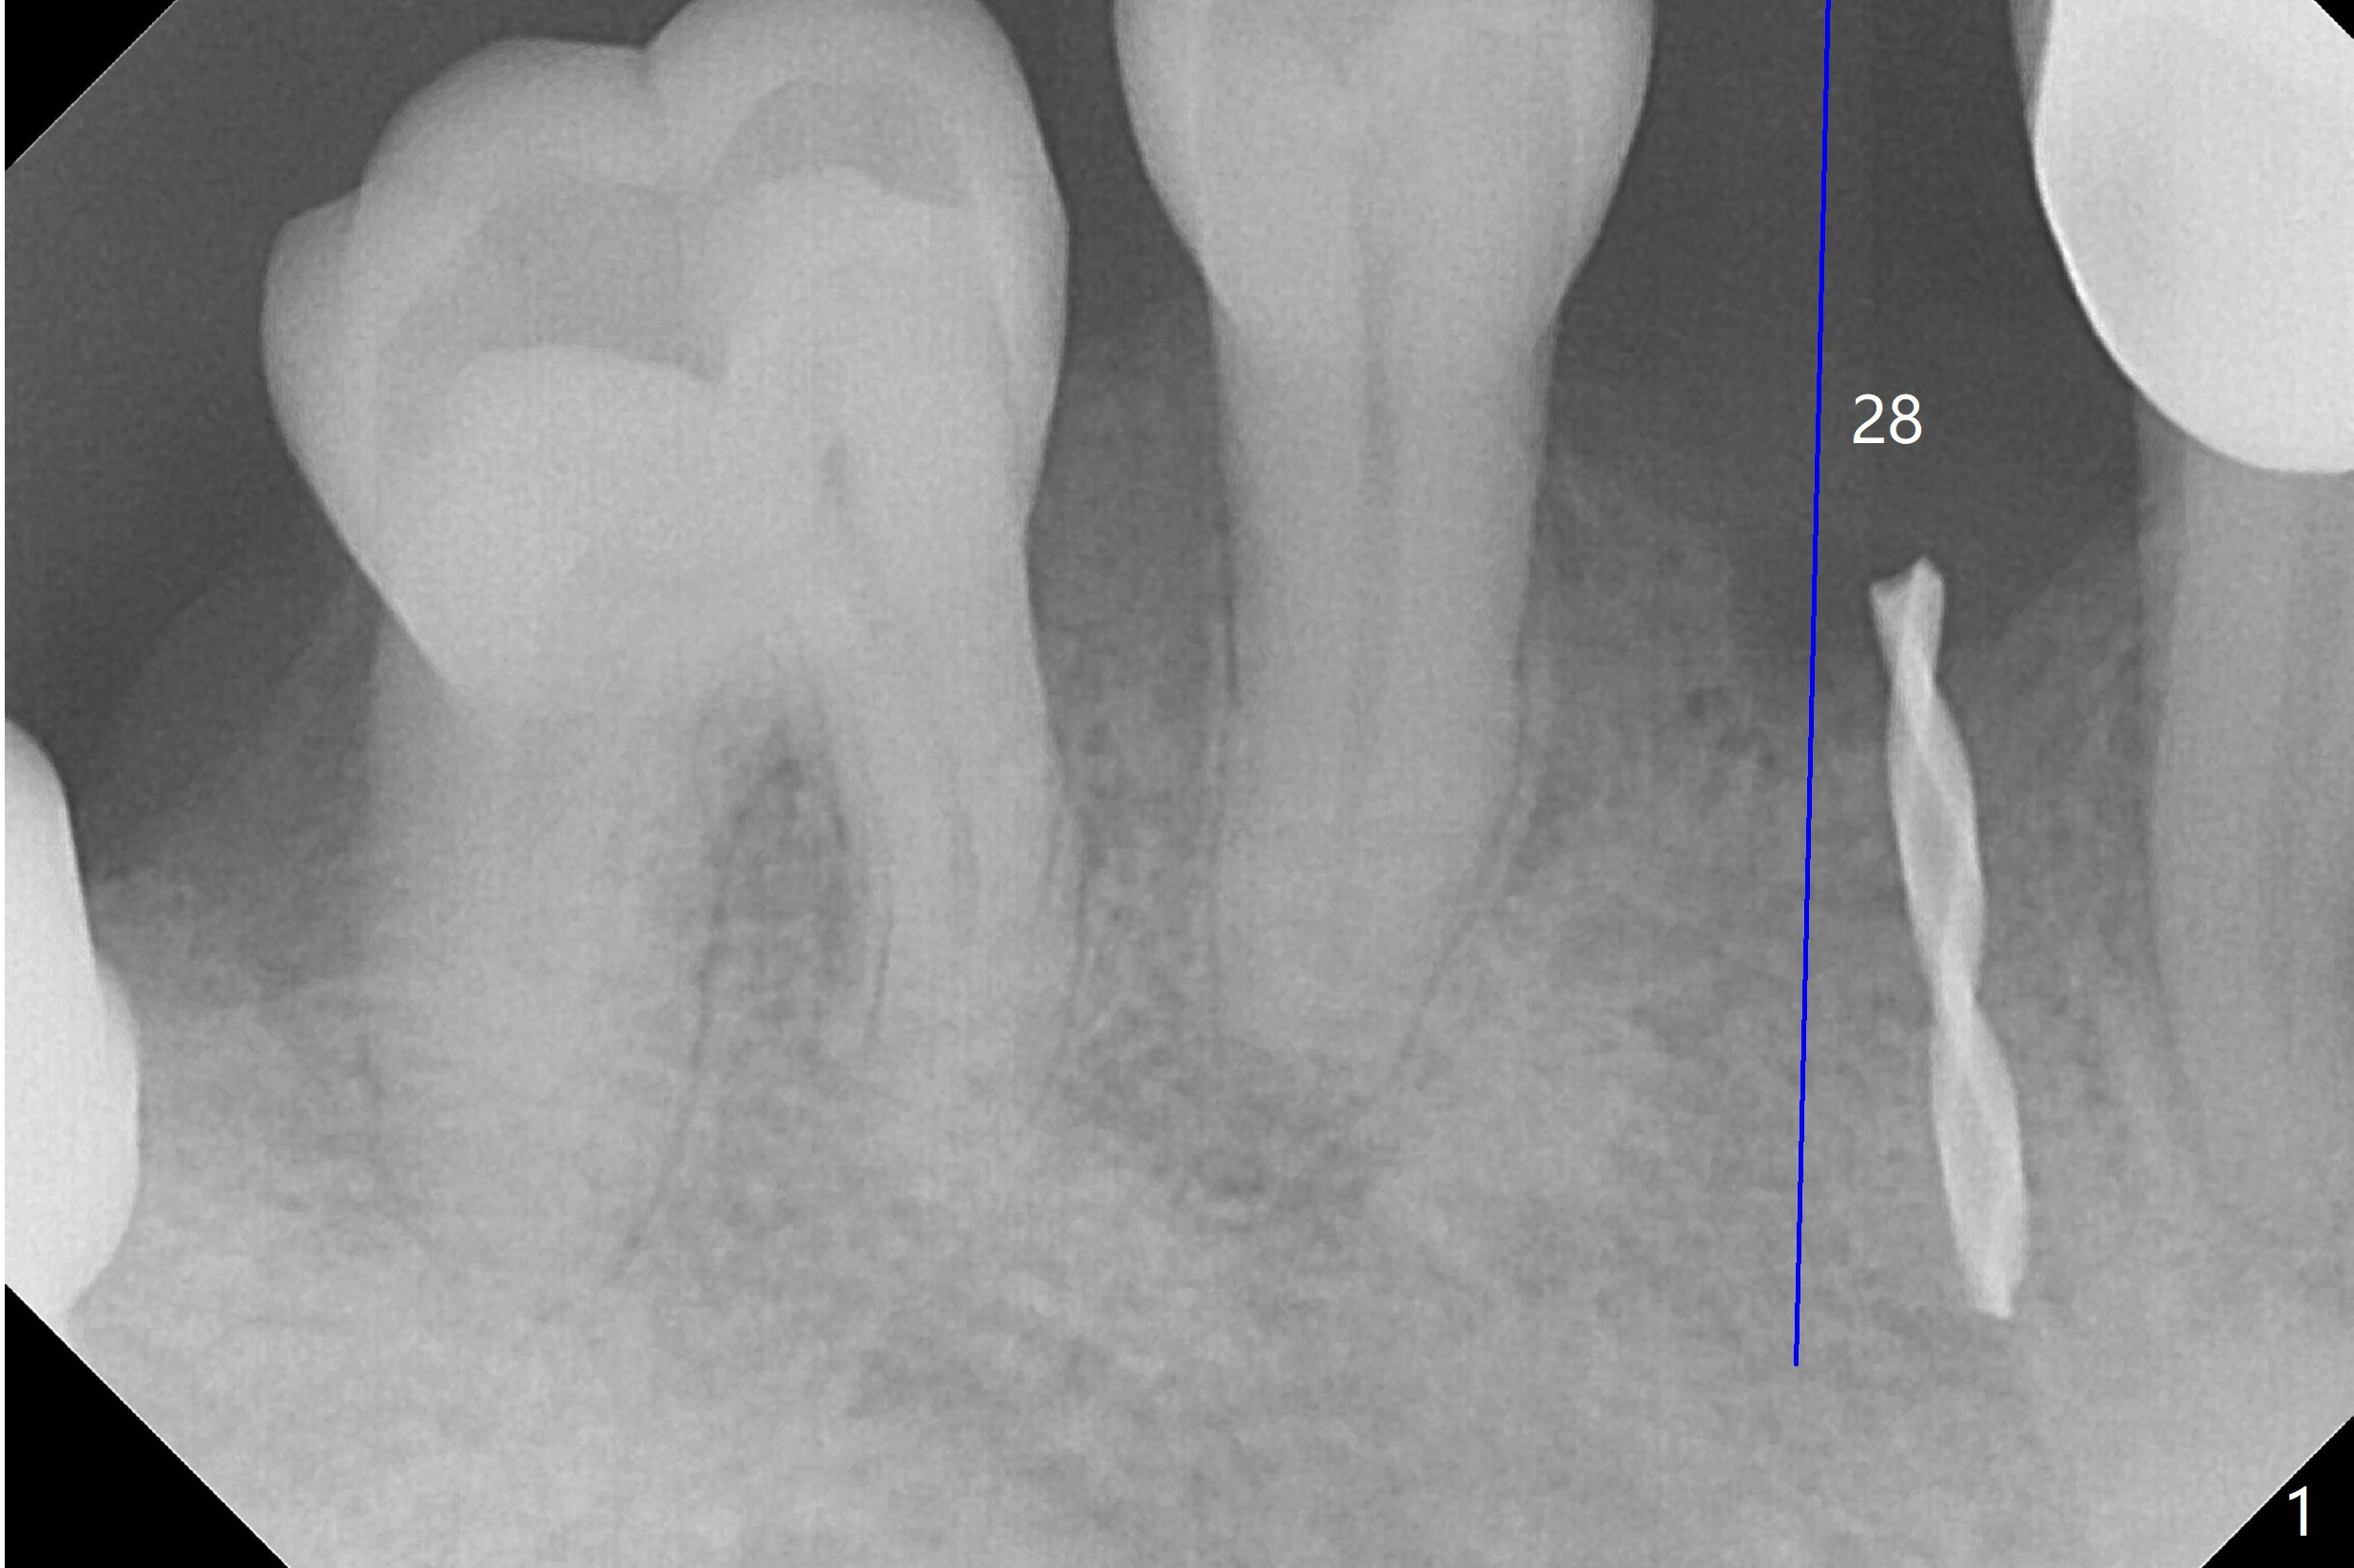

When flaps are raised at #28, the ridge appears to be narrow. Severe ridge resorption occurs 1-2 years post exfoliation. After ridge reduction, osteotomy is initiated mesially (Fig.1 (broken drill as a parallel pin)). A new osteotomy is going to be initiated as indicated by a blue line in Fig.1. It is done close to what is expected (Fig.2). When a 2.5x10(4) mm 1-piece implant is placed <20 Ncm, a major concern is where the Mental Loop is. To answer the question, intraop CBCT is taken (Fig.4). It appears that the ridge has not resorbed. If palpate more lingually (Fig.4 white <), the ridge would be found not so narrow. Preop and intraop panoramic X-ray film show sufficient bone height at the site (Fig.5,6). Low torque may be associated with low postop bone resorption, but it will take long to restore the implant.